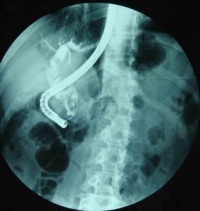

4.静脉胆道造影、PTC(经皮肝穿刺胆道造影术)、ERCP、CT等检查,显示胆管扩张,有结石影。可有胆总管下段部分梗阻、排空迟缓征象。

5.ERCP和PTC检查均可清晰显示胆管系统的全貌,能比较准确提供肝内外胆管和胆囊结石的大小、数量、位置以及肝内外胆管扩张、狭窄等病理改变状况,是获得术前准确诊断最重要的检查方法。ERCP基本无创、并发症较少,PTC为有创、并发症稍多,可根据病人和病变的具体情况选择。一般情况下多选择ERCP检查。

胆总管结石手术

胆总管探查取石放置“T”形管引流,是多年来传统的方法。可以有效防止胆汁外渗,避免术后胆汁性腹膜炎和局部淤胆感染,安全可靠,并可在术后通过“T”管了解和处理胆道残留结石等复杂问题。特别是我国原发性胆管结石发病率高,并存肝内胆管结石和肝内外胆管扩张狭窄等复杂病变者较多,很难保证胆总管探查术中都能完善处理。因此大多数情况下仍应放置“T”形管引流为妥。“T”形管材料应选择乳胶管,容易引起组织反应,一般在2~3周可因周围粘连形成窦道。用硅胶管或聚乙烯材料的T形管,组织反应轻,不易形成窦道,拔管后发生胆汁性腹膜炎的机会较多,不宜采用。“T”形管的粗细,应与胆总管内腔相适应。经修剪后放入胆总管的短臂直径不宜超过胆管内径,以免缝合胆管时有张力。因为张力过大、过紧,有导致胆管壁血供不足或裂开、胆汁溢出和日后发生胆管狭窄。若有一定程度胆总管扩张者,最好选用22~24F的“T”管,以便术后用纤维胆道镜经窦道取石。缝合胆总管切口,以2-0或3-0号的可吸收线为好。因为丝线等不吸收线的线结有可能进入胆总管内成为结石再发的核心。胆总管缝合完成后,可经T管长臂,轻轻缓慢注入适量生理盐水试验是否缝合严密,若有漏水应加针严密缝合,以免术后发生胆汁渗漏。关腹前将“T”管长臂和肝下腹腔引流管另戳孔引出体外,以免影响腹壁切口一期愈合。 3.腹腔镜胆总管探查取石主要适于单纯性胆总管结石,并经术前或术中胆道造影证明确无胆管系统狭窄和肝内胆管多发结石者。因此这一方法多数为继发性胆总管结石行腹腔镜胆囊切除术时探查胆总管。切开胆总管后多数需要经腹壁戳孔放入纤维胆道镜用取石网篮套取结石,难度较大,需要有熟练的腹腔镜手术基础。取出结石后可根据具体情况决定直接缝合胆总管切口或放置“T”形管引流。